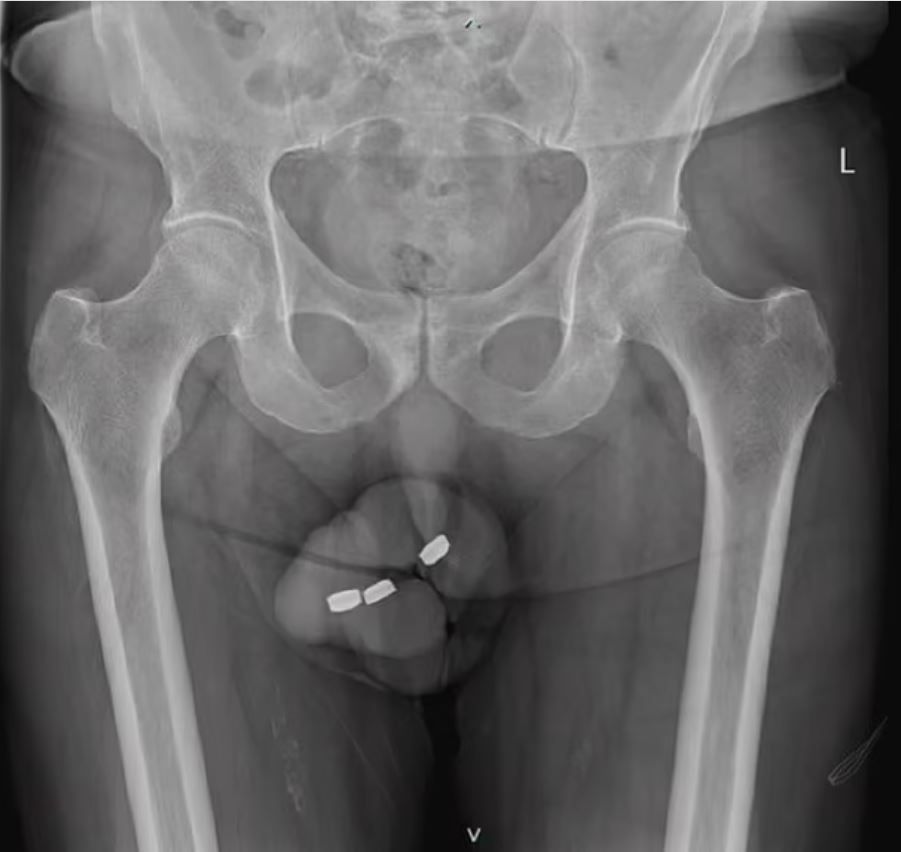

▲老翁在下體塞入3顆鈕扣電池,導致陰莖燒傷被迫切除部分組織。(圖/Urology Case Reports)

澳洲一名老翁因為患有勃起功能障礙,自作聰明拿鈕扣電池「入珠」,將3顆寬1.3公分的電池塞入陰莖內。然而由於電池卡在體內時釋放出腐蝕性液體,導致老翁的陰莖大規模燒傷,等到他因為無法排尿就醫時,陰莖內部已經嚴重壞死,因此醫師最終只能將部分尿道切除,並且勸他放棄陰莖全面重建手術。

醫生指出,老翁塞入尿道內的鈕扣電池寬約1.3公分,當時他們試圖用醫療鉗取出電池,但一度讓電池卡在尿道更深處。當鈕扣電池卡在身體內部時,會釋放出腐蝕性液體,可能在數小時內導致組織和血管燒傷,引發嚴重內部損傷和出血,進而致命。